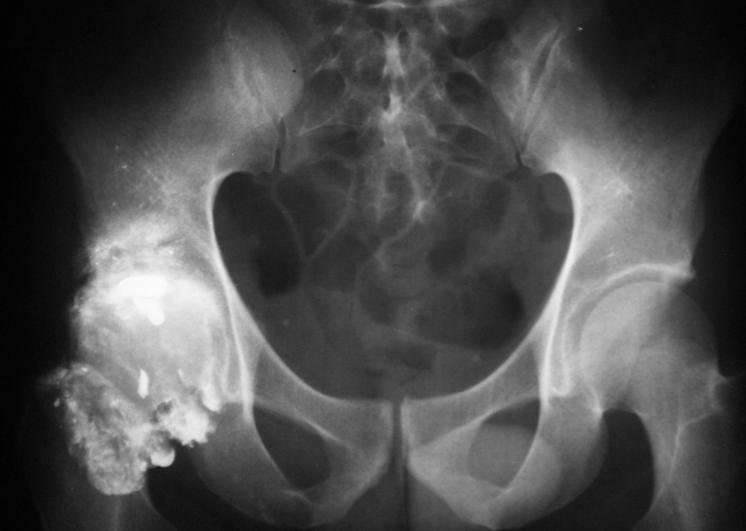

Gunshot wounds to the hip region are likely to cause complex peritrochanteric fracture. Treatment by early stable fixation and bone grafting. There is no consensus, however, on the use of antibiotics for these. The fracture patterns are often highly comminuted. Gun shot wounds are high energy injuries that contribute to extensive soft tissue damage and comminuted bony fractures.

Gunshot Wound Orthobullets . Gunshot wounds to the hip region are likely to cause complex peritrochanteric fracture. Treatment by early stable fixation and bone grafting. There is no consensus, however, on the use of antibiotics for these. Gun shot wounds are high energy injuries that contribute to extensive soft tissue damage and comminuted bony fractures. The fracture patterns are often highly comminuted.